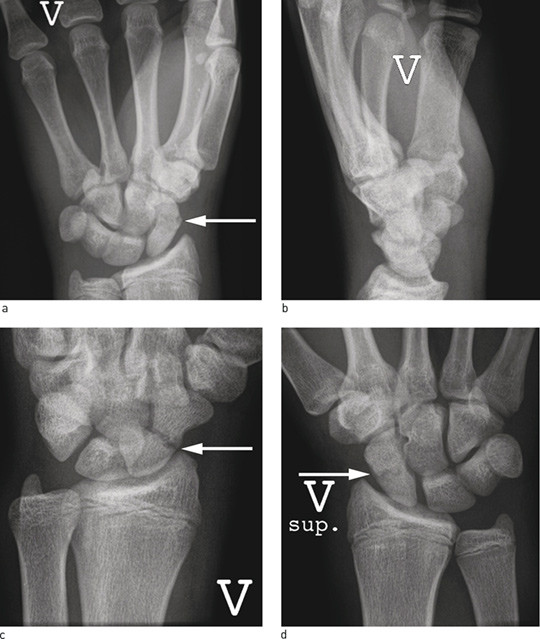

De fire radiologiske standardprojeksjonene (fig 2) avslører de fleste frakturer, men noen brudd er ikke synlige på initiale bilder. Pasienter med positive kliniske funn og negative funn på røntgenbilder må derfor følges videre. De kan enten avklares umiddelbart med MR/CT eller gipses og kontrolleres klinisk og røntgenologisk etter to uker. Ved fortsatt klinisk mistanke og negativt røntgenbilde tas CT eller MR slik at fraktur kan bekreftes eller avkreftes (fig 3). MR og CT har begge 100 % sensitivitet. CT vil bedre avsløre dislokasjon og tegn på eldre fraktur eller pseudartrose (10). Om man har mulighet, bør man avklare problemstillingen umiddelbart med supplerende bildediagnostikk, slik at pasienten slipper unødvendig gipsimmobilisering. Se flytskjema for utredning av mistenkt skafoidfraktur (fig 4).